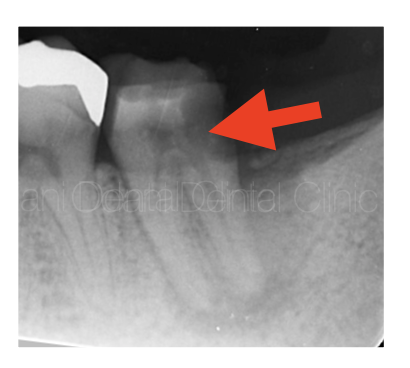

診察および画像検査の結果、歯の周囲を大きく取り囲むような黒い影(黄色の矢印)が確認できました。

詰め物を外すと中で大きな虫歯が生じており(赤矢印)、そこから神経が死んでしまい、歯の周囲にまで細菌感染している状態だと判断できました。骨の支えが大きく失われており、歯は大きく揺れておりました。

歯の保存が困難となる可能性も高い状態で抜歯もよぎりましたが、根管内の細菌が原因(専門的病名としては歯内歯周複合病変)と診断し、相談の上で保存の可能性にかけて感染根管治療を行うこととなりました。